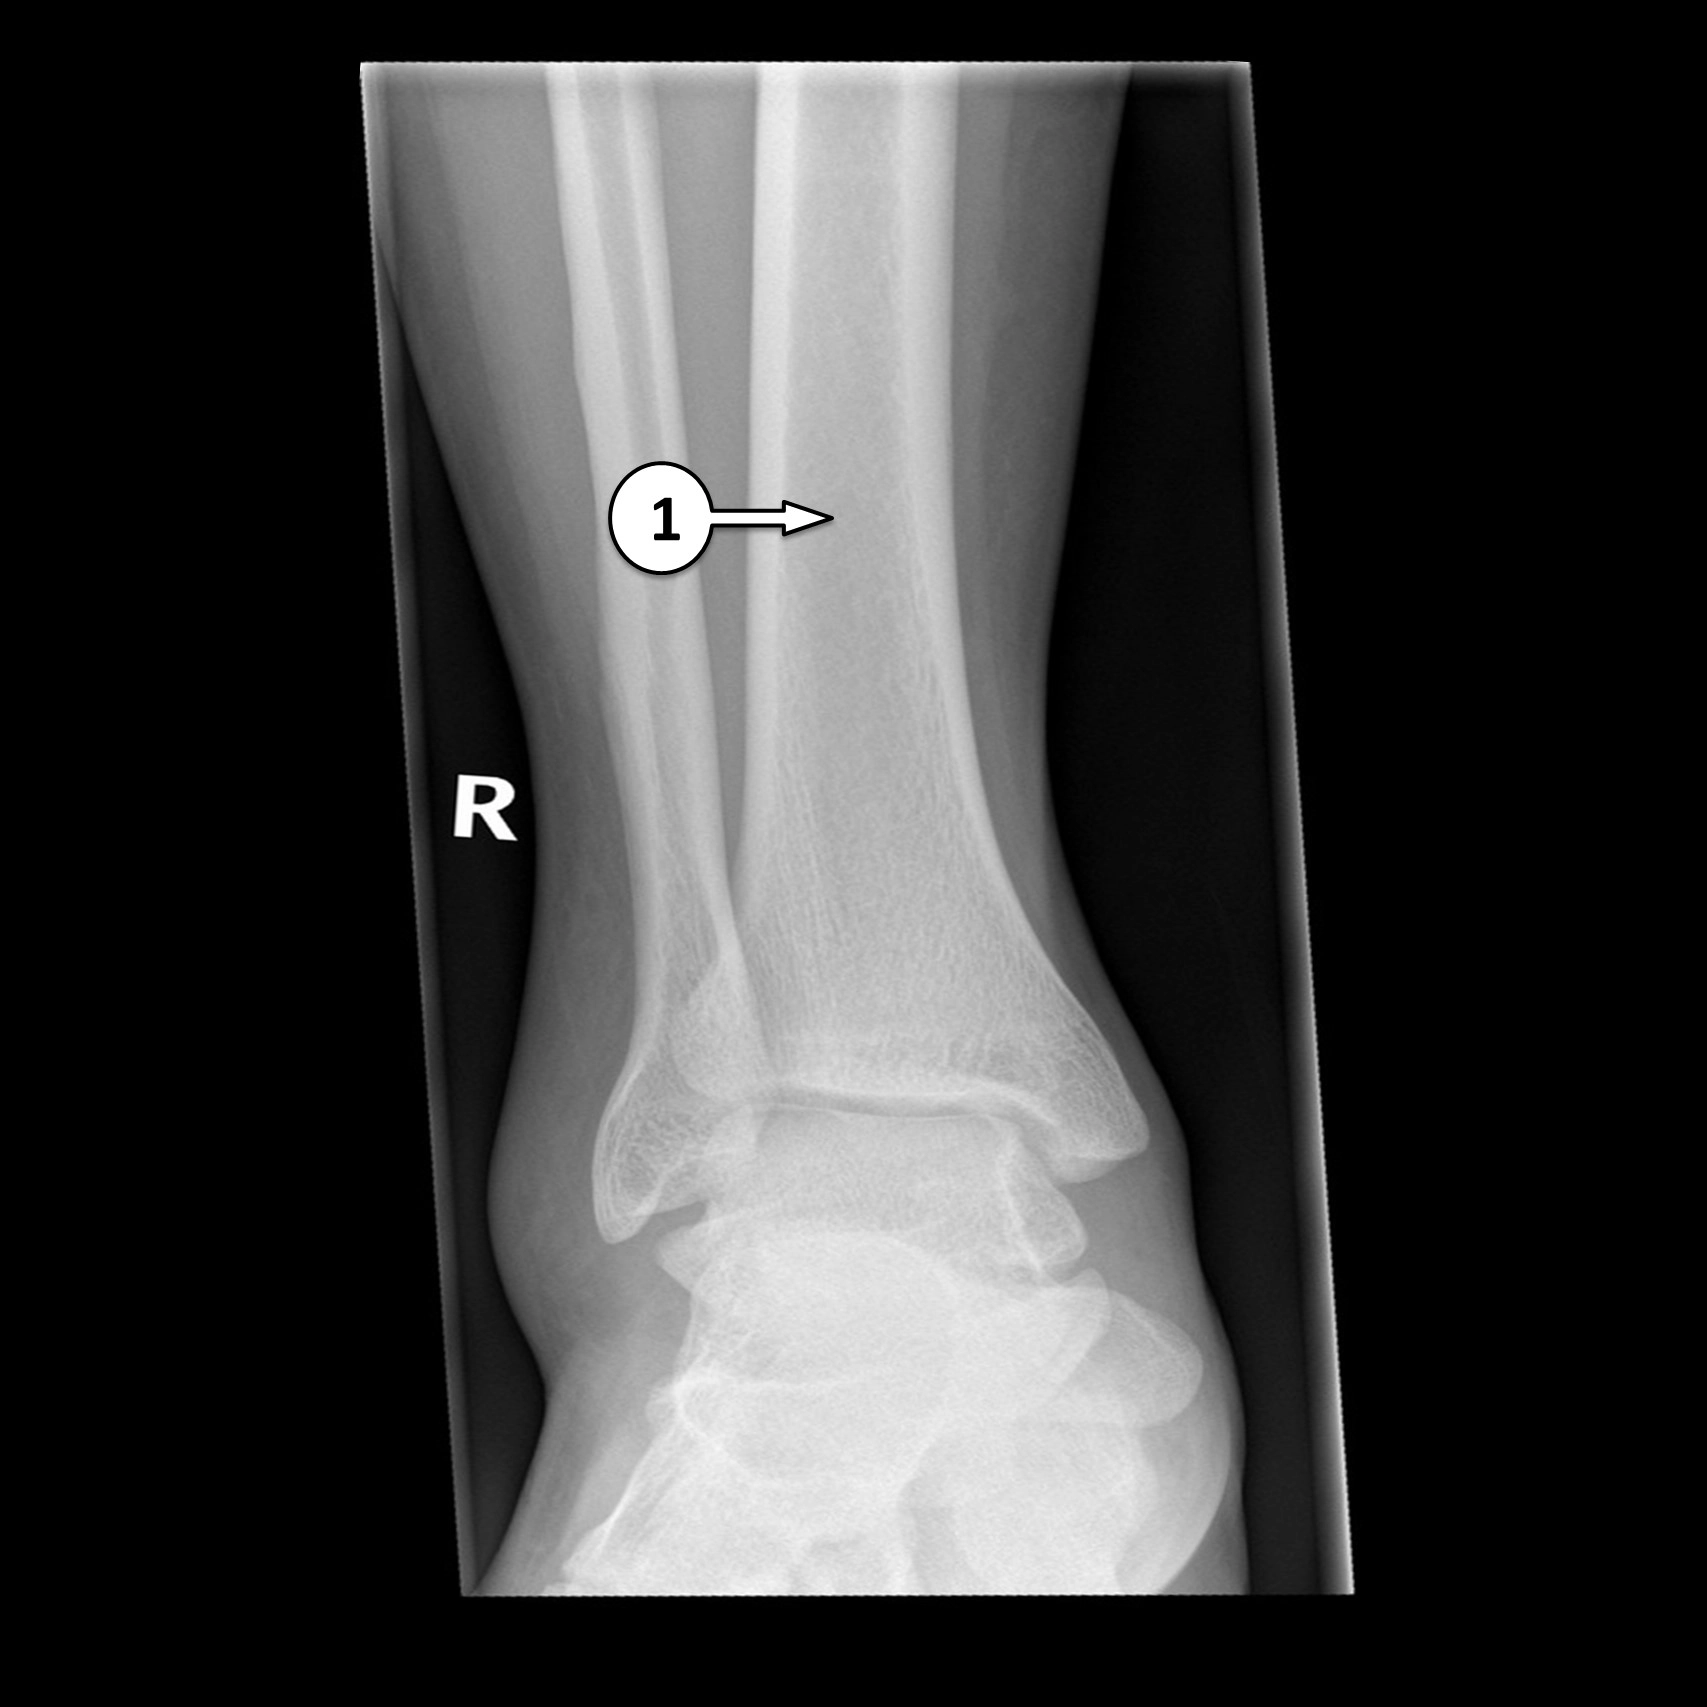

X Quang xương cổ chân

16/03/2026